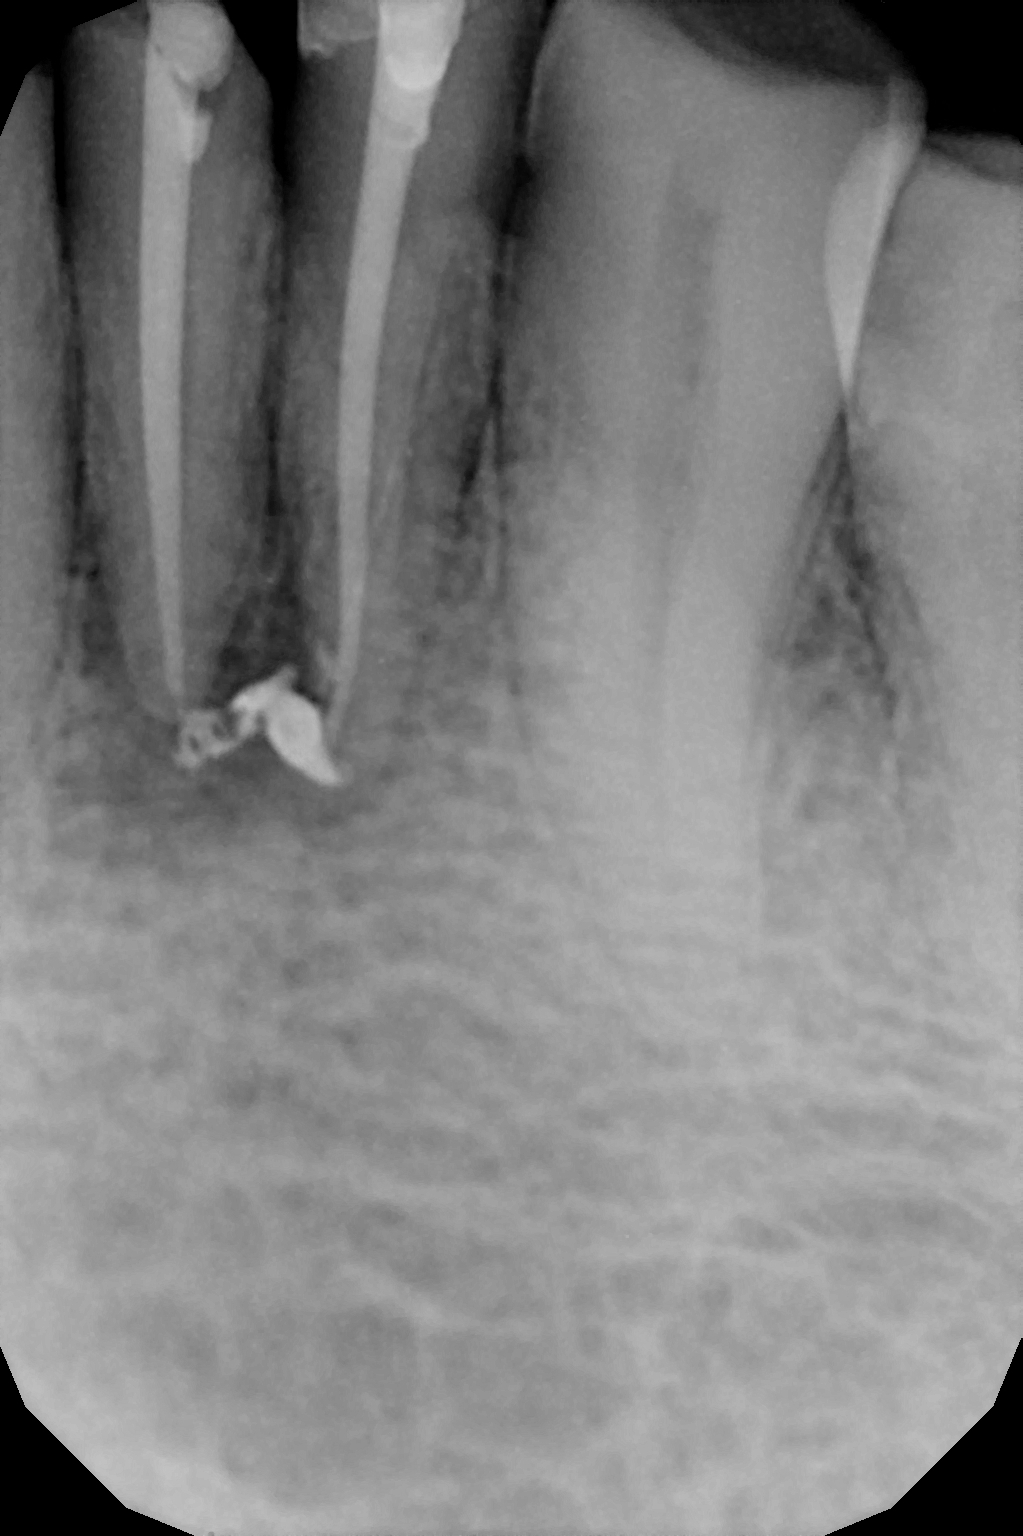

When the tooth is is sensitive to particularly hot and cold. When you cannot chew from that side or there is associated action of pain and swelling with same tooth, root canal treatment can save the tooth. For root canal treatment our clinic is equipped with state-of-the-art facility. We are following the protocol that is universally accepted and considered as a gold standard We are using rubber Dam for maximum possible cases. The root canal treatment is done under local anaesthesia that's why mostly it is painless . The rubber Dam isolation helps in proper irrigation and it provides much needed ease to the operating dental surgeon and the patient . The sealer and filling material are one of the Prime requisite of quality root canal treatment, it needs use of multiple X rays to really judge whether the results are acceptable or not. In older days root canal was just about cleaning the decade portion, removing the Pulp and filling it with biocompatible material but nowadays the root canal treatment it is very much advanced the precision is increased manifold. The materials and armamentarium that is required for efficient root canal have advanced in exclusion initial ways the the Abstract of all these things is the patients are getting great results after root canal treatment. Only the root canal is not sufficient to make a tooth functional again ,it needs use of Core buildup material and complete coverage Crowns according to the tooth position. During Covid19 time we have studied and implemented use of of high strength composites in our practice and the results of it are amazing many times it has saved tooth from being restored with crown. In some cases where the tooth is grossly carious we need a complete coverage crown. The materials and the Crown materials are are available in various price ranges. We prefer only the best of materials for our patients. We believe that to perform best treatment we need best of the armamentarium and best of the material for our patients who value and deserve the best of the treatment.